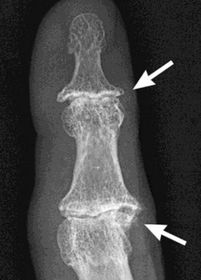

| What disease is this? What indicates this? | Tophaceous gout. Soft tissue swelling surrounding the index finger PIPJ, with associated erosion and bone resorption |

| What disease is this? | Tophaceous gout. |